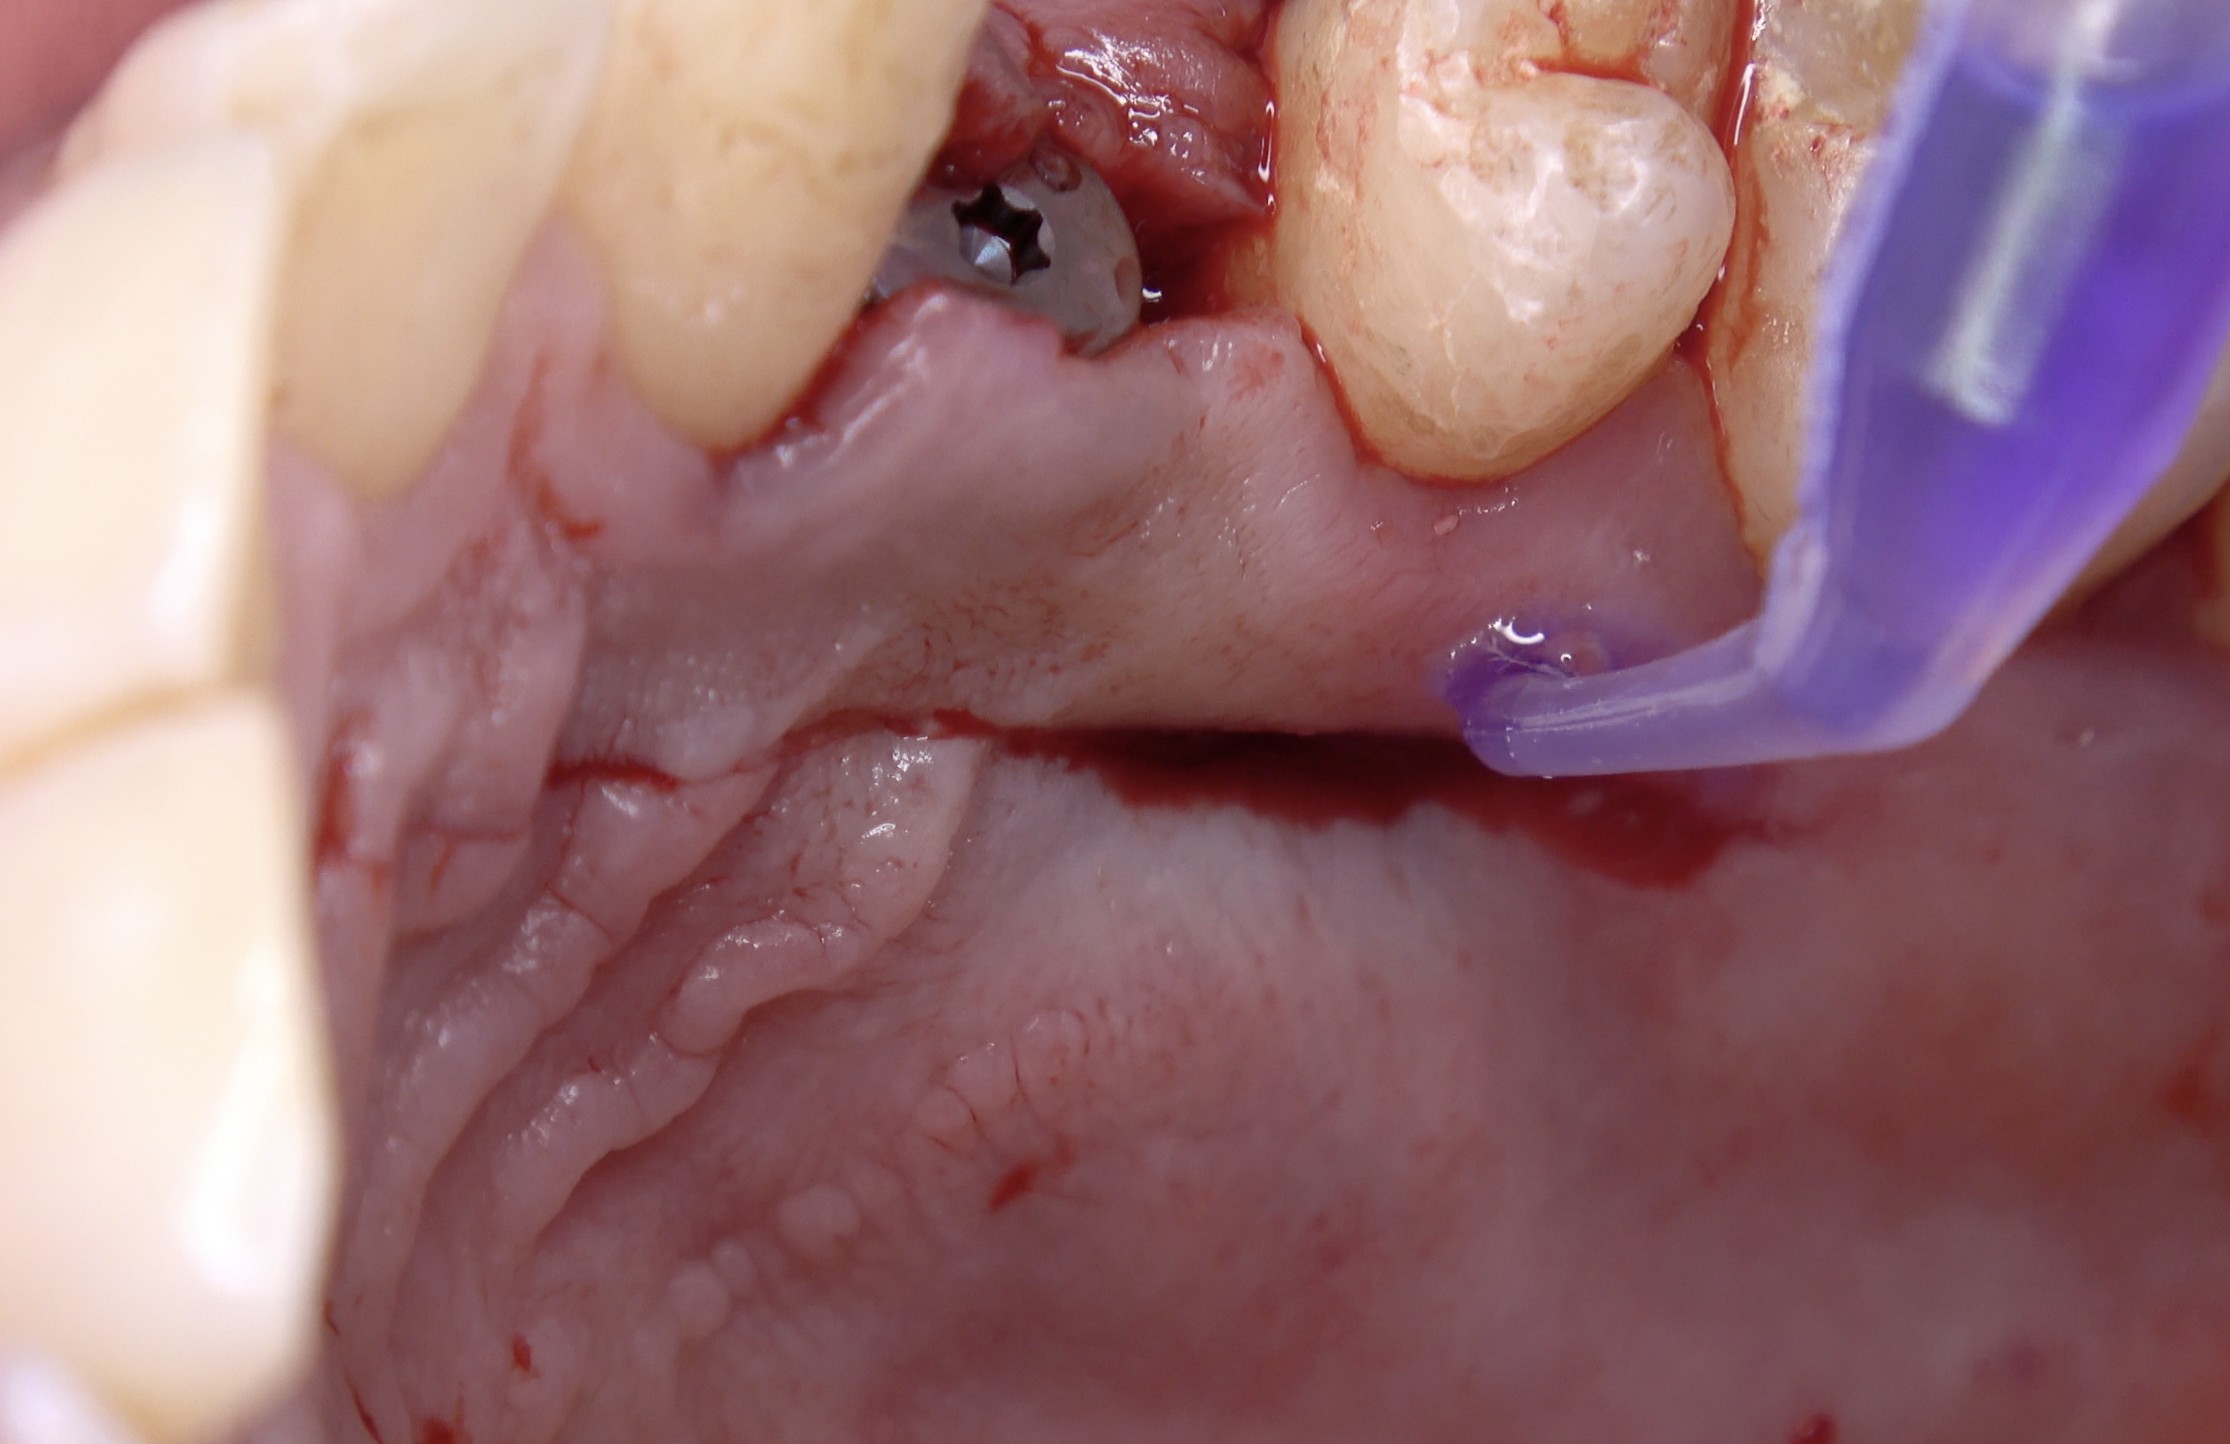

Métodos: Se llevó a cabo un caso clínico en una paciente de 40 años con fracaso de restauración fija dentosoportada en el incisivo central superior izquierdo, asociado a caries radicular subgingival con mal pronóstico restaurador. Tras la evaluación clínica y radiográfica, se indicó la exodoncia atraumática del diente afectado. Inmediatamente después, se realizó la colocación de un implante postextracción. El defecto periimplantario (gap) fue rellenado con un xenoinjerto óseo bovino. De forma simultánea, se llevó a cabo un injerto de tejido conectivo con el objetivo de optimizar el volumen y la estabilidad de los tejidos blandos periimplantarios. Se procedió a la colocación de una restauración provisional inmediata atornillada, diseñada para preservar el perfil de emergencia y guiar la cicatrización de los tejidos periimplantarios. Tras un periodo de cicatrización de cuatro meses, se colocó la restauración definitiva atornillada.